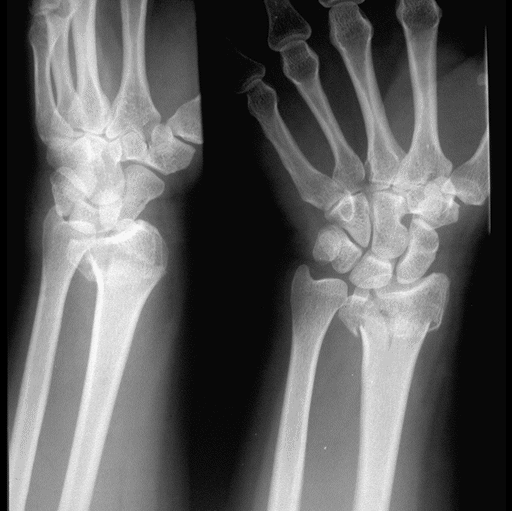

Case 2 Preop